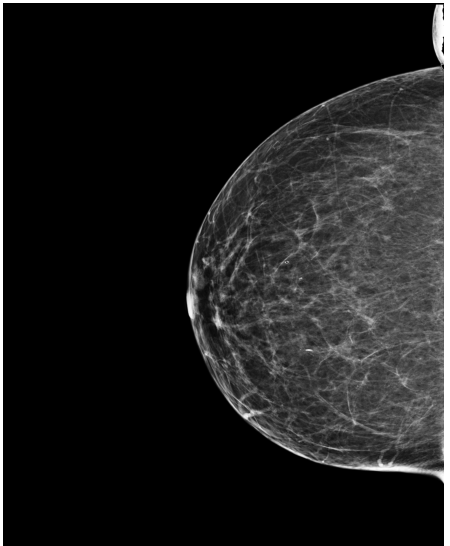

4.3 Pre-processing

The EMBED and CSAW-CC datasets originally consist of images in DICOM format, which are converted into 16-bit grayscale PNG images for consistency and compatibility. Following the pre-processing procedure outlined in (Yala et al.,, 2021), we enhanced image quality and removed background artifacts—such as textual annotations commonly present in mammography images—by applying a contour detection procedure. All contours in the image are detected, and only the largest contour, corresponding to the breast tissue, is retained. This contour is then used to create a mask that isolates the breast region from the background. The isolated breast image is resized to a size of 1664×20481664\times 2048 pixels while preserving the aspect ratio. Finally, the resized image is normalized and converted to a 16-bit format.